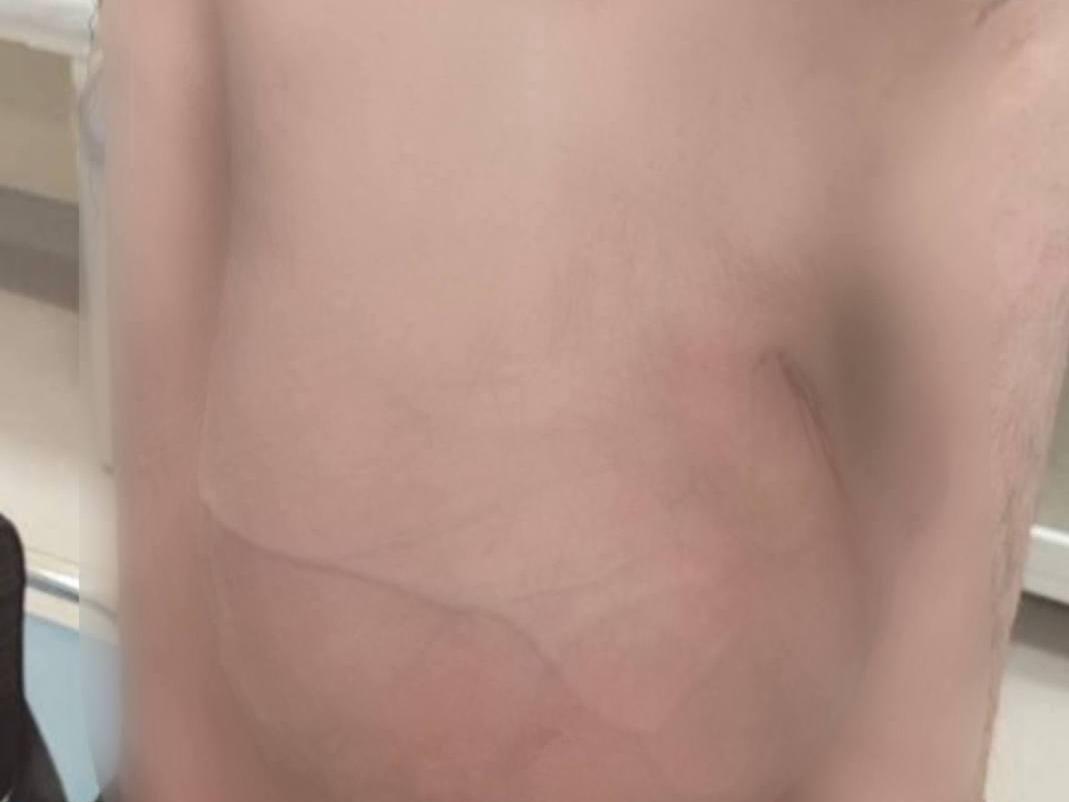

The man was admitted to the clinic on the eve of the New Year holidays. The formation, measuring 40 × 50 × 40 cm (about 16 × 20 × 16 inches), contained almost the entire intestine, had descended into the scrotum, and severely hindered movement. The operation was performed by specialists from the first surgical department under the guidance of Professor Andrey Demko. Despite the complexity of the case, the patient was discharged in satisfactory condition on the ninth day. The clinical case was reported only after confidence in the absence of long-term complications.

The technically challenging task was to return the intestinal loops to their anatomical place without a large-scale incision of the abdominal wall. After that, the surgeons restored normal anatomy and reinforced the area with a mesh implant to prevent recurrence.